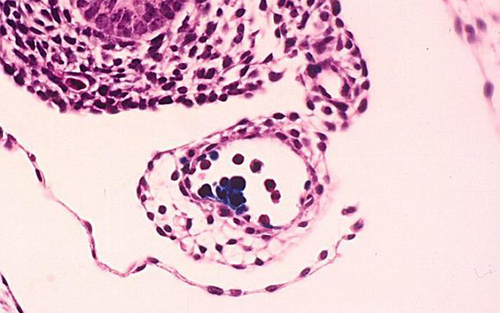

这意味着基因突变并不会导致疾病,同时对于科学家提供人类长寿的重要线索。骨髓中的造血干细胞使人类血液不断地补充更新,细胞分裂很容易被人们错误理解,包括血液在内的多数细胞分裂很有可能形成基因突变。严重骨髓性白血病等血癌患者体内存在着数百个基因突变,但科学家并不清楚是否健康白血球细胞也存在基因突变。这项研究是由美国冷泉港实验室研究人员负责的,他们对这位超级女寿星的白血球细胞基因序列进行研究分析,确定她一生中是否体内健康白血球细胞累积基因突变。

科学家在女寿星体内白血球细胞中发现400多个基因突变,但突变并未存在于她的大脑,据悉,大脑是自出生之后很少出现细胞分裂的身体组织。

通过检查这些白血球细胞是否包含基因突变,研究人员获得了暗示人类寿命上限的重大发现。研究报告负责人亨纳-霍尔斯特格(Henne Holstege)博士称,我们非常吃惊地发现女寿星死亡的时候,周边血液干细胞仅由两个活跃造血干细胞衍生。

霍尔斯特格博士强调,由于血球细胞具有非常短的染色体端粒,我们猜测多数造血干细胞可能死于“干细胞衰竭”,它们抵达干细胞分裂上限。